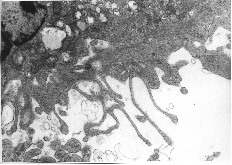

Fig. 8A: This figure which corresponds to Video sequence 6, with D T2 = 2 hrs, shows a capillary crowded with erythrocytes. Two thrombocytes are situated in close contact with the endothelial lining of the capillary. Nuclei of endothelial cells are not seen in this section. The cytoplasmatic processes of endothelial cells seem to constitute parts of a "normal" capillary wall. The piling up of erythrocytes was also recorded in the vitalmicroscopic studies of this and neighbouring vessels, all with unusually low blood flow. The possible adhering of a thrombocyte to the endothelial lining, as indicated in this picture, may be among the first signs of generation of a thrombus.

Fig. 8C: This figure which corresponds to Video sequence 3, with D T2 = 48 hrs, demonstrates a thrombus with a massive aggregation - particularly of platelets - and the presence of fibrin, giving rise to the useful, but somewhat imprecise term "platelet plug".